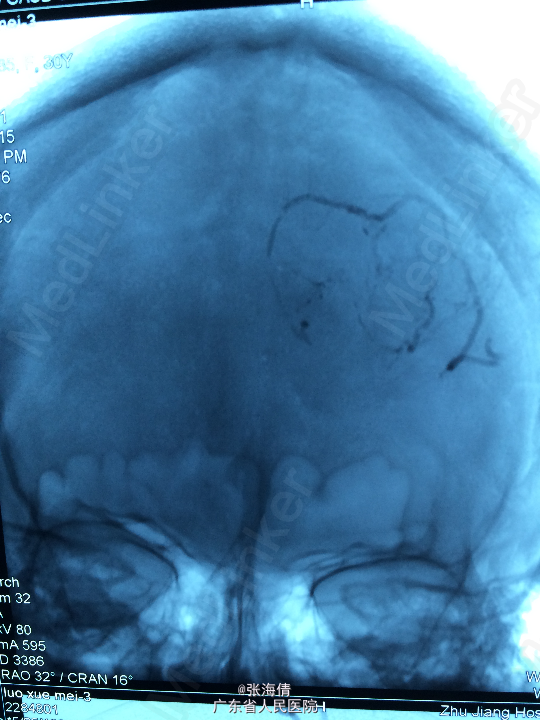

主诉:头晕、恶心6h 病史:患者男,22岁,2年来头晕、恶心症状多次出现,发作频率无明显规律,每次约2 min,无其他不适。6小时前上述症状加重,伴呕吐,呕吐物为胃内容物,外院CT平扫:示右侧颞顶叶见结节状稍高密度影,外院MR提示:平扫示右颞顶叶可见结节状稍长T1混杂T2信号影,大小约2.5 cm×2.1 cm×2.6 cm,边界较清晰,周围见长T1长T2水肿信号,SWI序列病变内未见明显低信号,DWI示信号稍高,增强扫描明显均匀强化,可见分叶,右侧脑室后角轻度受压

查体:全身未触及明显肿大淋巴结。脑膜刺激征:颈项强直,Kernig’S征阳性。 辅助检查:外院CT平扫:示右侧颞顶叶见结节状稍高密度影,外院MR提示:平扫示右颞顶叶可见结节状稍长T1混杂T2信号影,大小约2.5 cm×2.1 cm×2.6 cm,边界较清晰,周围见长T1长T2水肿信号,SWI序列病变内未见明显低信号,DWI示信号稍高,增强扫描明显均匀强化,可见分叶,右侧脑室后角轻度受压

诊断:脑膜瘤 处理:先予DSA以明确肿瘤供血情况,术中脑膜瘤供血丰富,用PVA颗粒超选到供血动脉将其闭塞。后再择期在气管全麻下行脑膜瘤切除术。